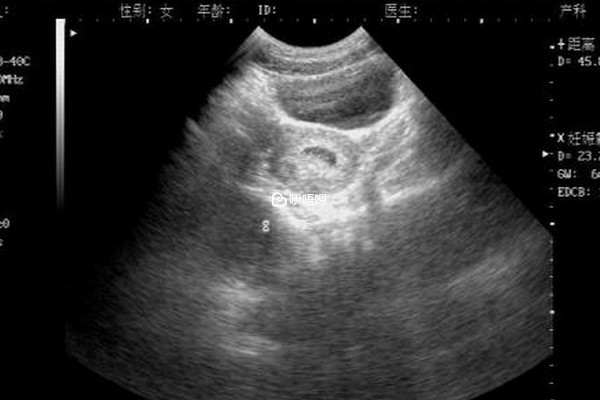

胎囊主要是從胎囊形狀、大小、長寬等3個數據來看生男生女的,但目前這種方法也有很大的弊端,因為胎囊的發育還受到很多因素的影響,而且從孕6-7周的孕囊的形狀也根本判斷不出胎兒是一個男孩還是女孩,並且b超只是影像學,會受到胎兒體位以及生殖器大小的影響,誤差是避免不了的。

網傳孕囊三個資料看男女準確率高達90%,但是種方法實際在嘗試的過程中準確度並不高,因為檢查孕囊的目的主要是看胎兒的生長髮育情況,資料體現的也是寶寶的健康狀況,基本沒有暗示胎兒的性別,只能說方法可以嘗試但結果不能當真。

現在判別生男孩女孩的辦法有許多,比方懷孕40天,經過晨尿和酒精、妊娠線、孕肚形狀、b超檢單等,但這些都沒有科學依據,現在最精確、最科學的辦法只要四種,精確率在90%以上,如b超、絨毛取樣、DNA驗血、羊膜穿刺術。

胎囊3個數據看生男生女的方法

- 胎囊的長度寬的相距在一倍以上,那麼男孩子可能性大,但如果長度寬相同,或是相距並不大得話,很可能是個女寶;

- 如果胎囊檢查結果中,如果胎囊呈現長條形狀,生男寶寶的概率大,如果孕囊長和寬相差不大,呈橢圓形或圓形,生女寶的概率大;

- 一般情況胎囊資料相差大的生男孩,資料相差小的生女孩,如39mmX30mmX25mm生男孩,35mmX34mmX28mm生女孩。

其實通過胎囊3個數據看男女的準確率並不高,但目前國家規定非醫學目的分辨胎兒男女性別是犯法的,因此,醫院是不會通過任何途徑告訴暗示胎兒性別的,其實不管在懷孕期間注意胎兒的健康發育就可以,男孩還是女孩都是一樣的。